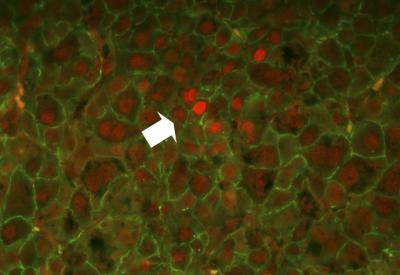

Liver cells rely on signals triggered by growth hormone to survive and multiply—functions that go haywire in cancer. Normally, growth hormone works by activating a signaling network inside liver cells that includes a protein called STAT5. When the researchers removed STAT5 from liver cells, cancer ensued.

The normally protective effect of STAT5 was traced to its ability to hitch itself to a damage-inducing protein called TGFbeta and trigger its destruction. Without STAT5, TGFbeta levels soared, and growth hormone activated a related protein, STAT3, which is known to promote tumor growth.

TGFbeta and STAT5 appear to be adversaries in the liver, according to the study. STAT5 protects the liver by breaking down TGFbeta. But when TGFbeta is abundant—as occurs in people with chronic liver damage—growth hormone activates the cancer-promoting STAT3 instead of the protective STAT5. These results might help explain how chronic liver damage can eventually lead to cancer.